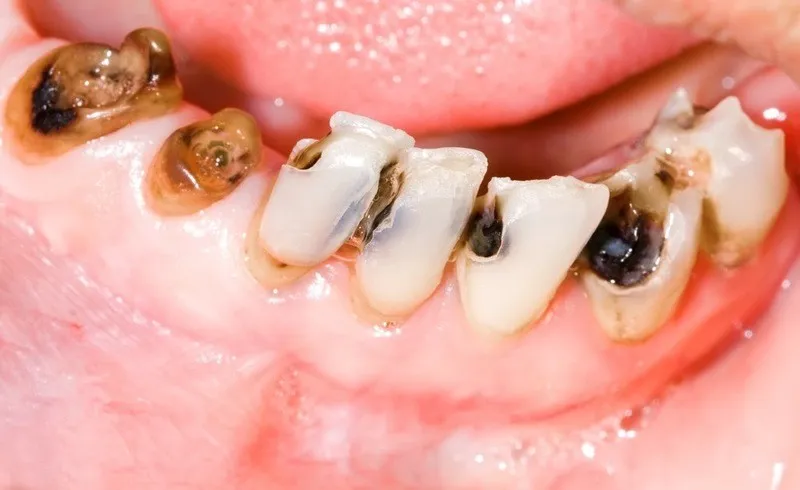

Sâu răng

Sâu răng là một vấn đề nghiêm trọng trong nha khoa. Nó xảy ra khi răng bị tổn thương do vi khuẩn tấn công qua việc ăn uống không đúng cách. Đồng thời thường xuyên tiêu thụ đồ ngọt và thiếu vệ sinh răng miệng hợp lý. Khi sâu răng không được điều trị kịp thời, phần mô răng bị hủy hoại dần theo thời gian. Từ đó sẽ khiến phần thân răng bị tiêu biến. Lúc này chỉ còn lại chân răng nằm dưới lợi. Nếu không can thiệp điều trị sớm, tình trạng này sẽ dẫn đến việc mất răng vĩnh viễn.